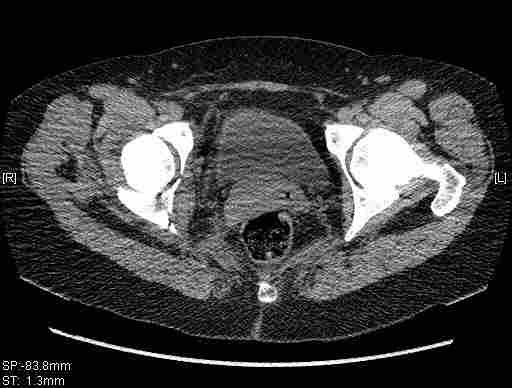

[Ortho] [1/2] Re: Т-образный перелом вертлужной впадины

Удалось сегодня вывести пациентку в соседнюю больницу, где есть кт.

Срезы сделаны  только горизонтальные.